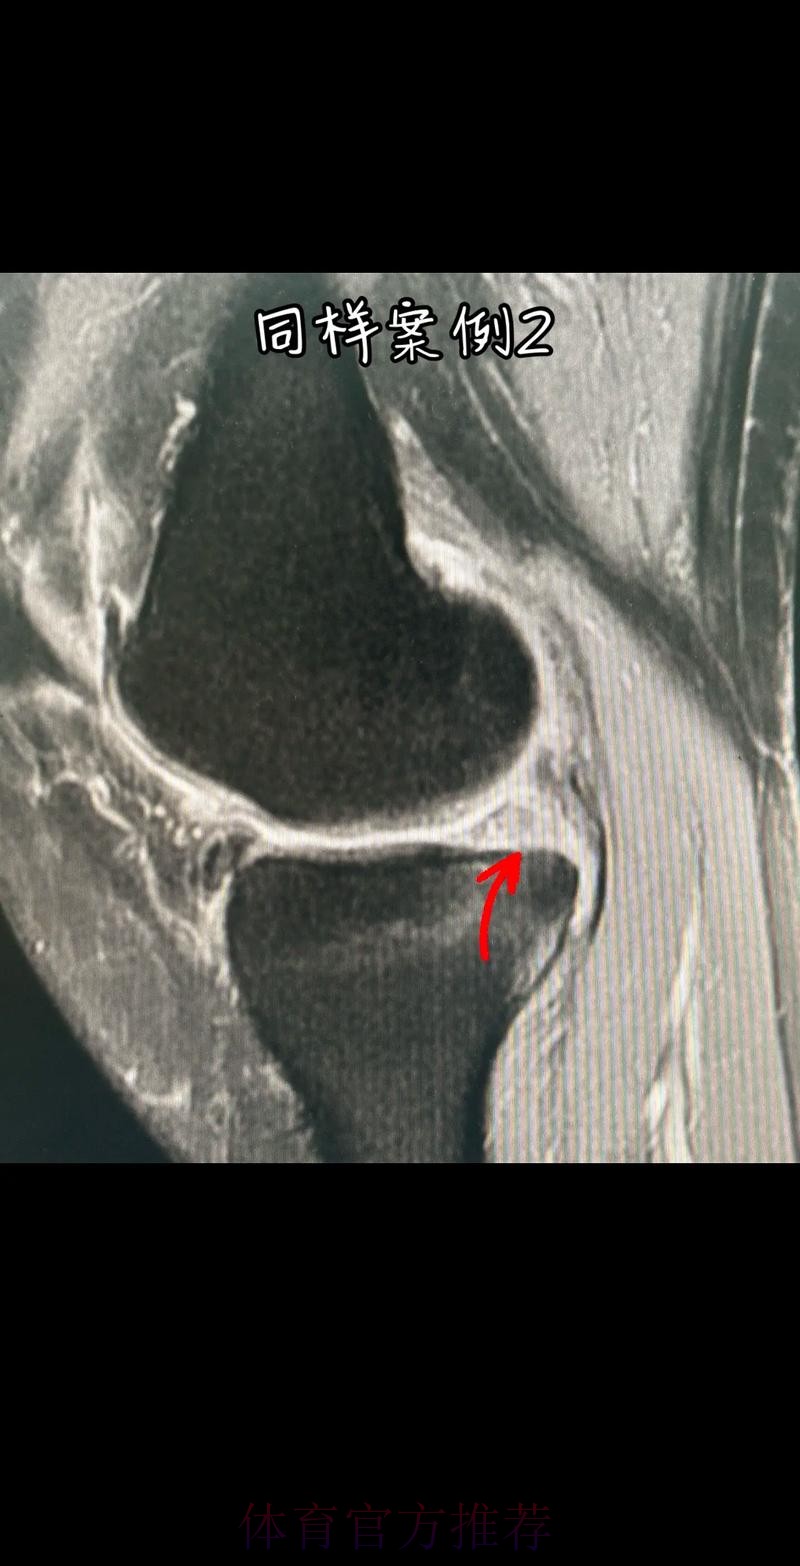

从医学角度看 半月板是膝关节内一块呈“C”形的软骨结构 其作用是缓冲冲击 稳定膝关节 并帮助分散压力 “左膝内侧半月板撕裂”通常说明在一次急停 旋转 或对抗中 半月板受到了超过其承受极限的力导致结构损伤 这类伤病常见于足球 篮球等需要频繁变向和对抗的项目 对于职业球员而言 半月板损伤严重程度不一 但共同点是都会影响支撑发力 跳跃以及变向时的稳定性 而官方给出的“预计伤缺6-8周”这个时间区间 往往对应的是中度损伤或通过微创手术加积极康复能够较快回归的情况 也意味着暂时没有出现必须长时间休战的最坏结果 表面上看 6-8周只是一个时间区间 但对顶级球队的赛程来说 这段时间可能包含多场联赛 甚至关键杯赛淘汰轮 相当于缺席一个赛季中最密集的一段周期 需要强调的是 这个“预计”并不是绝对数字 它取决于撕裂的位置 大小 修复方式 以及球员个体的恢复能力 有时若采取保守治疗 球员在6周时即可参与部分训练 但要达到比赛要求则可能接近8周甚至稍长 此外 精英运动员的康复不仅仅是伤口愈合 还包括力量恢复 协调重建 和心理自信的回归 阿拉巴要在有限时间内完成从“伤病患者”到“可靠首发”的角色转换 这一过程复杂程度远远超出一纸通告所能呈现